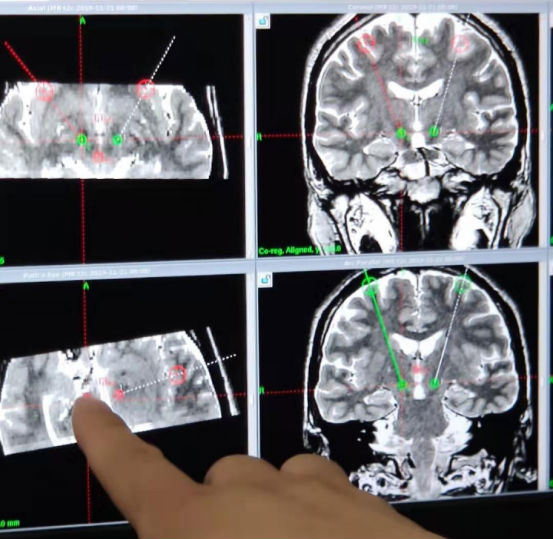

术前定位靶点和穿刺路径

24日,市第一人民医院神经外科专家在北京天坛医院神经外科专家的指导下,结合术前头颅核磁和手术当天头颅CT,计算机工作站通过图像融合技术,由Leksell头架定位出丘脑底核具体靶点,在立体定位下将电极深植入患者丘脑底核,经过3个多小时的手术,成功实施了双侧STN-DBS电极植入术+刺激器植入手术。经术中检测,电刺激器工作正常,患者四肢震颤、僵直症状明显改善。